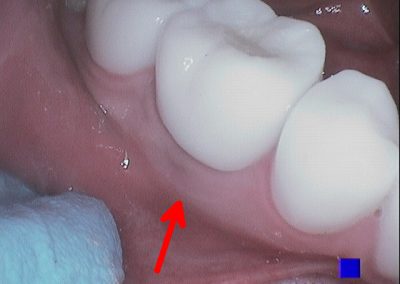

Before commencing the treatment, a local anaesthetic is administered and later a protective non-latex rubber sheet is placed around the tooth to prevent saliva contaminating the tooth and at the same time improves patients comfort.

After a few weeks, the tooth will be checked and when all the infection has cleared, a crown will be usually required to protect the restore the tooth to function.